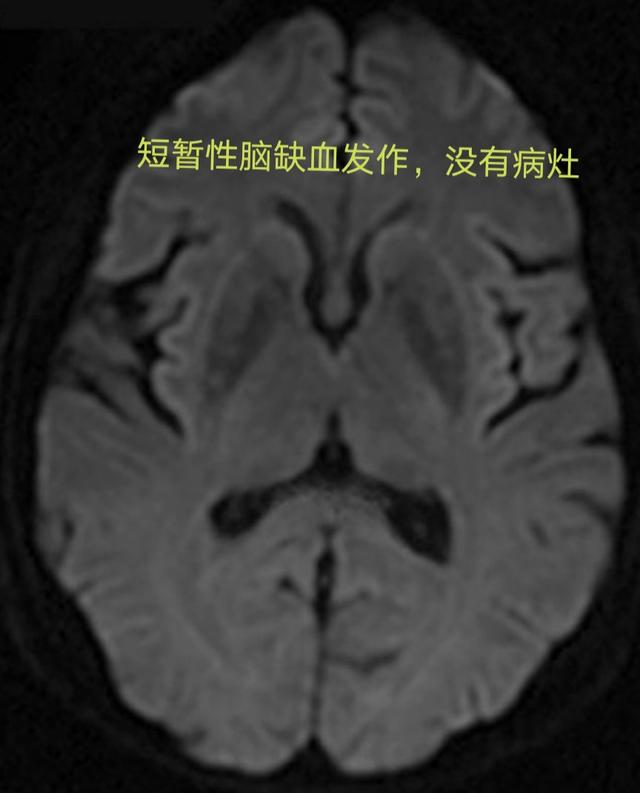

Attaque ischémique transitoire (AIT)Il s'agit de l'apparition d'une circulation sanguine dans une partie du cerveau, de la moelle épinière ou de la rétine.blocage de courte duréeCela pourrait conduire àSymptômes de l'infarctus cérébral transitoire,Les symptômes sont légers et ne durent généralement que quelques minutes.Rapidement, les vaisseaux sanguins se sont rouverts d'eux-mêmes.Pas de lésions du tissu cérébral ni d'incapacité permanente。

Étant donné que la durée des symptômes chez les patients souffrant d'un accident ischémique transitoire n'est pas longue, la plupart des patients semblent normaux lorsqu'ils consultent le médecin, mais ils devraient également améliorer les examens tels que la tomodensitométrie crânienne ou l'imagerie par résonance magnétique. Si l'examen d'imagerie ne révèle aucune lésion d'infarctus cérébral, le diagnostic d'accident ischémique transitoire devrait être posé et, en même temps, une hémorragie cérébrale peut être exclue, car elle peut également présenter des symptômes similaires. À ce stade, bien que les symptômes aient été soulagés, cela ne signifie pas qu'aucun autre diagnostic et traitement n'est nécessaire, et il est encore nécessaire d'améliorer l'angiographie par tomodensitométrie, l'angiographie par résonance magnétique ou l'angiographie, etc., pour clarifier la gravité des lésions vasculaires dans la tête et le cou, afin de guider l'élaboration d'un plan de traitement raisonnable.Il est important de noter queAu stade précoce de l'infarctus cérébral, les foyers d'infarctus cérébral ne peuvent être détectés par le scanner ou l'IRM, et la durée maximale d'un accident ischémique transitoire est de 24 heures ; comment différencier un accident ischémique transitoire d'un infarctus cérébral au cours de cette période de 24 heures ? La résonance magnétique pondérée en diffusion permet de détecter les premiers foyers d'infarctus cérébral.